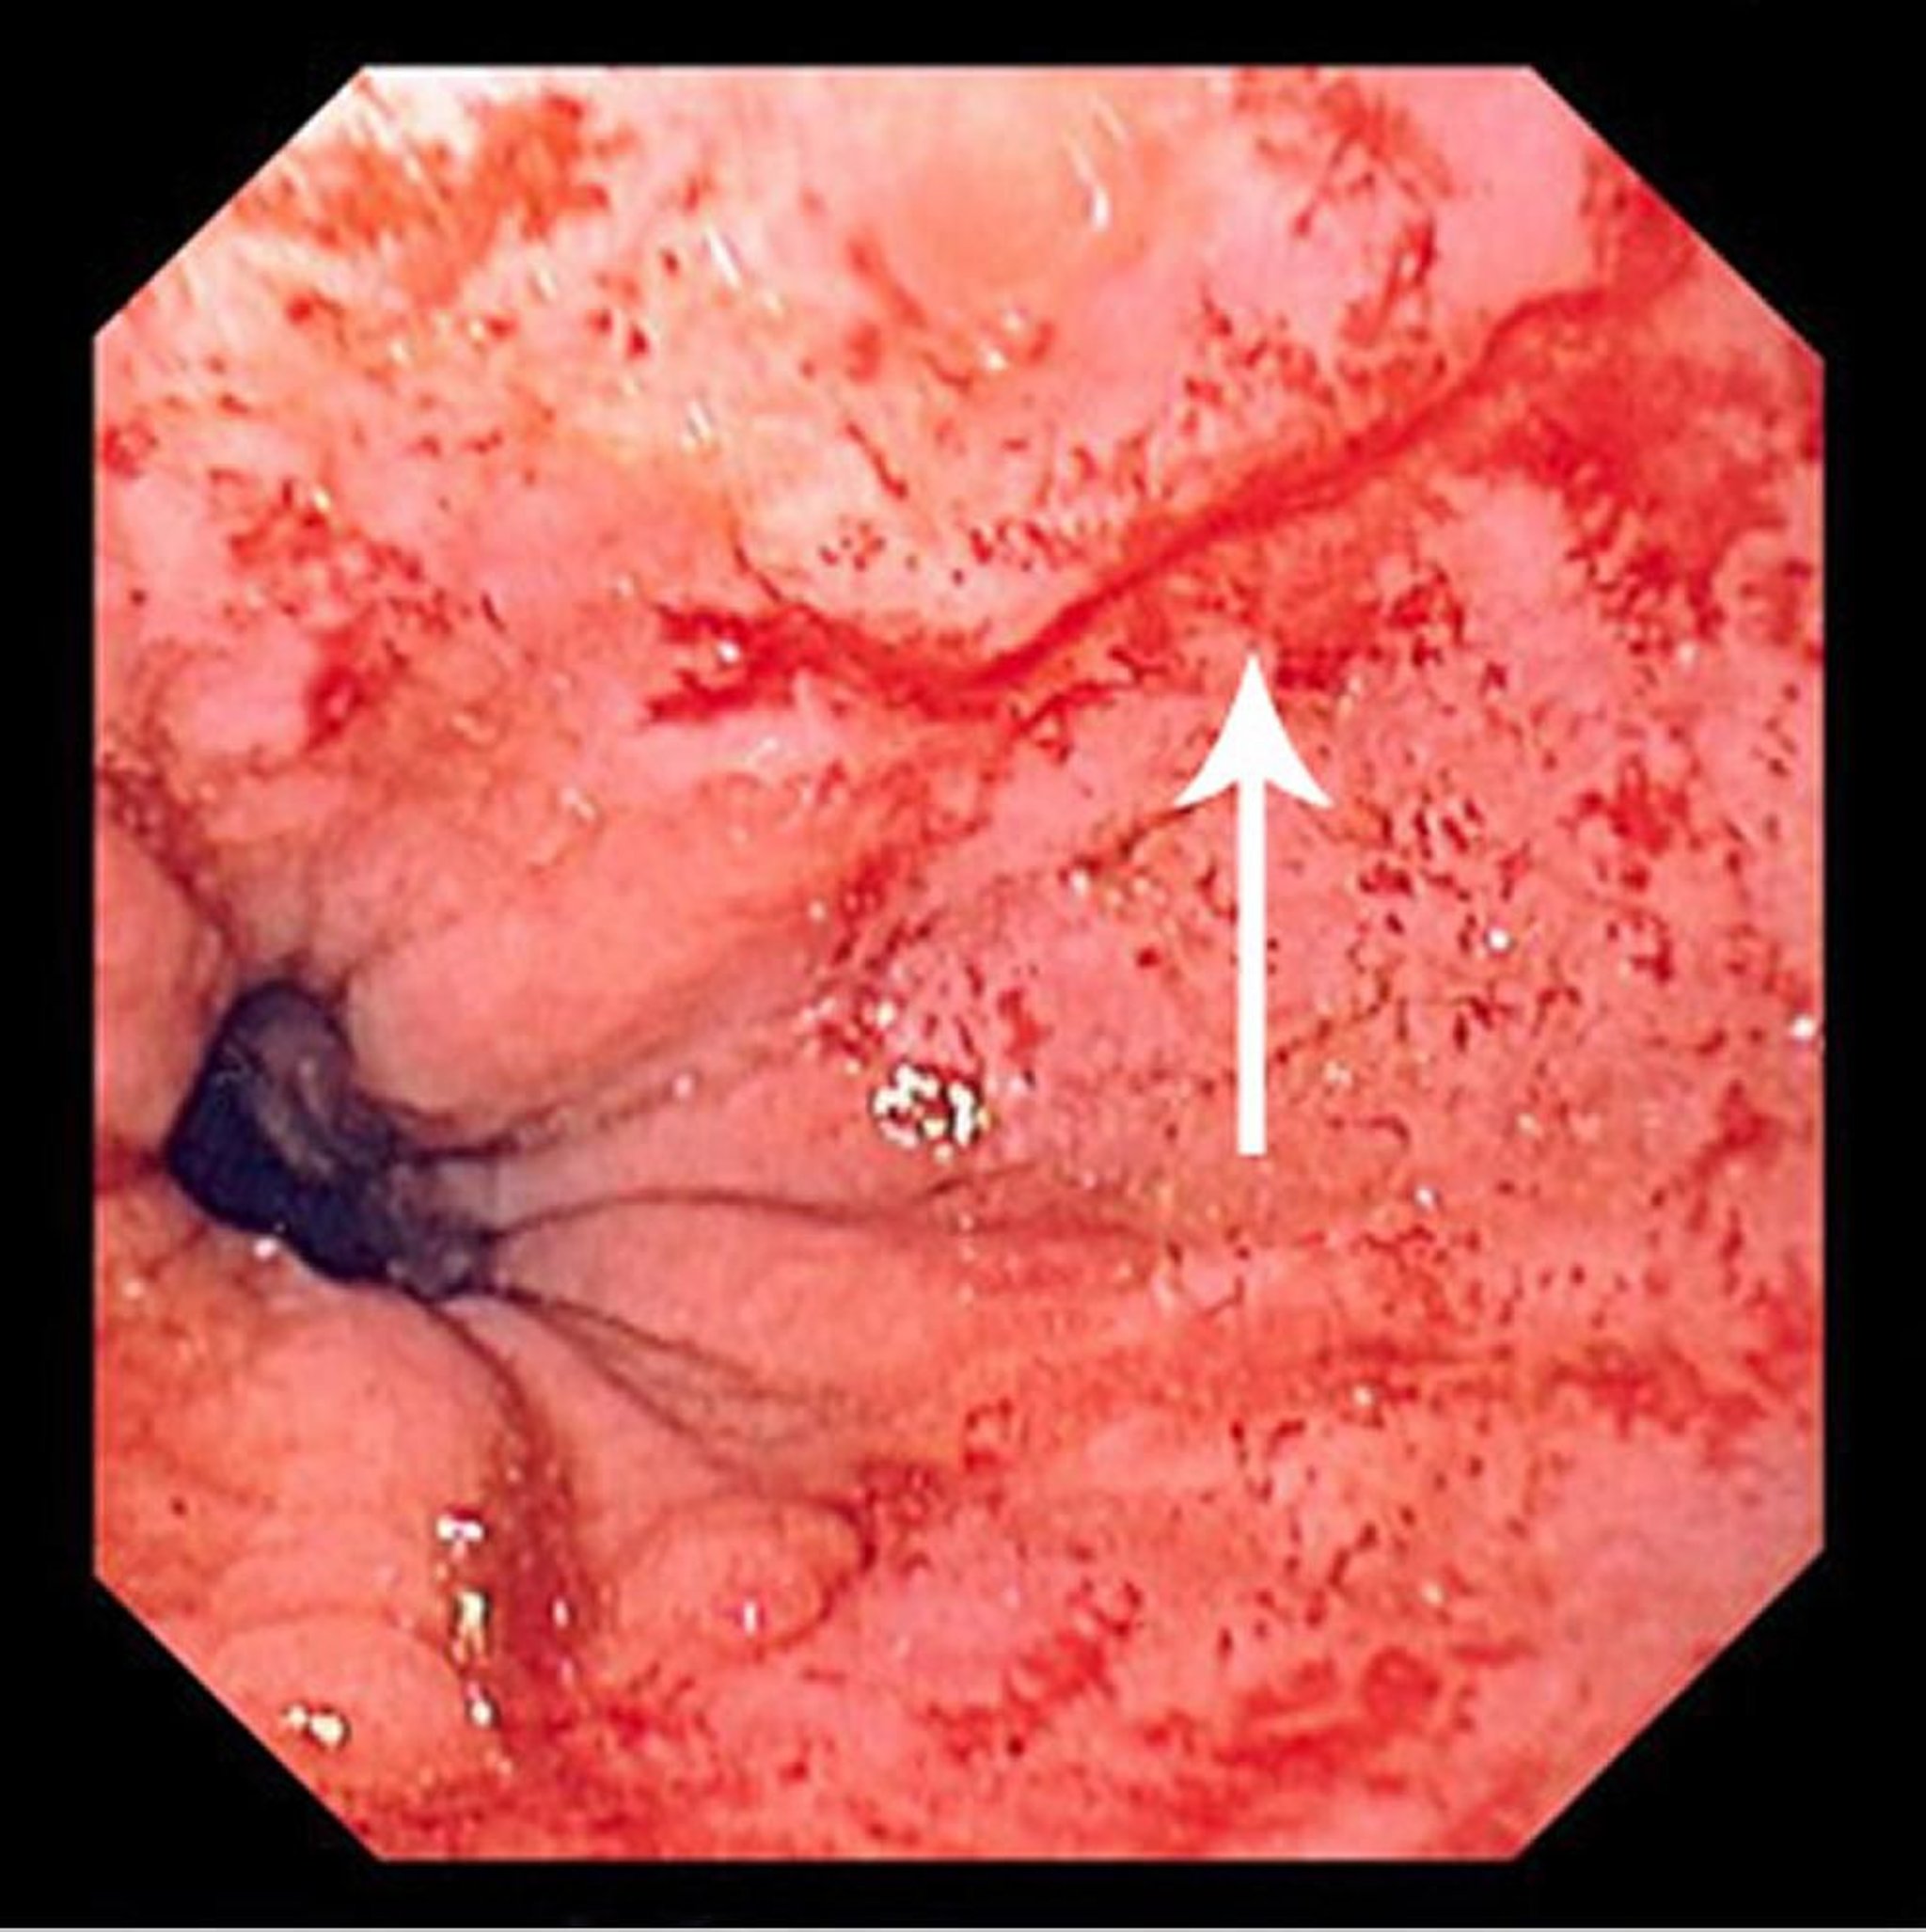

यदि खून का रिसाव गंभीर है या अपने-आप नहीं रुकता है, तो डॉक्टर अपर एंडोस्कोपी करते हैं। अपर एंडोस्कोपी के दौरान, डॉक्टर एंडोस्कोप नाम की एक लचीली ट्यूब का उपयोग करके इसोफ़ेगस की जांच करते हैं। अपर एंडोस्कोपी डॉक्टरों को खून के रिसाव के स्रोत को देखने देती है और अक्सर उसी समय में इसका उपचार करता है।